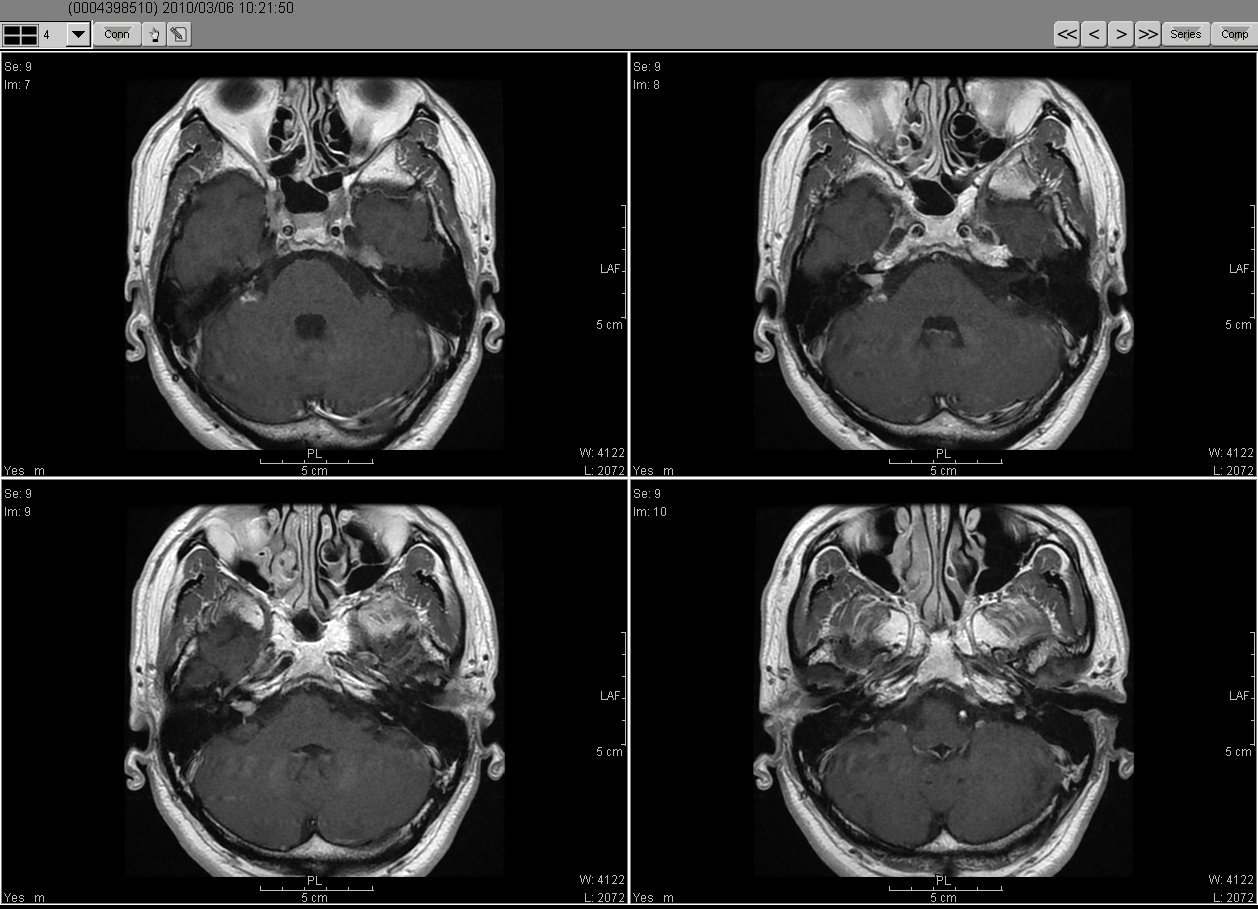

2010_03_06 MRI

2019_03_06MRI02